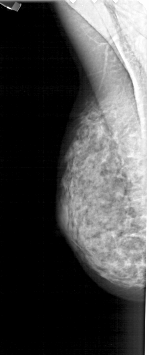

A_1269_1.RIGHT_MLO

A_1269_1.RIGHT_CC

RIGHT_MLO LINES 4726 PIXELS_PER_LINE 1831 BITS_PER_PIXEL 12 RESOLUTION 43.5 OVERLAY

RIGHT_CC LINES 3256 PIXELS_PER_LINE 1561 BITS_PER_PIXEL 12 RESOLUTION 43.5 OVERLAY

FILE: A_1269_1.RIGHT_MLO.OVERLAY

TOTAL_ABNORMALITIES 1

ABNORMALITY 1

LESION_TYPE CALCIFICATION TYPE PLEOMORPHIC DISTRIBUTION CLUSTERED

ASSESSMENT 4

SUBTLETY 3

PATHOLOGY BENIGN

FILE: A_1269_1.RIGHT_CC.OVERLAY